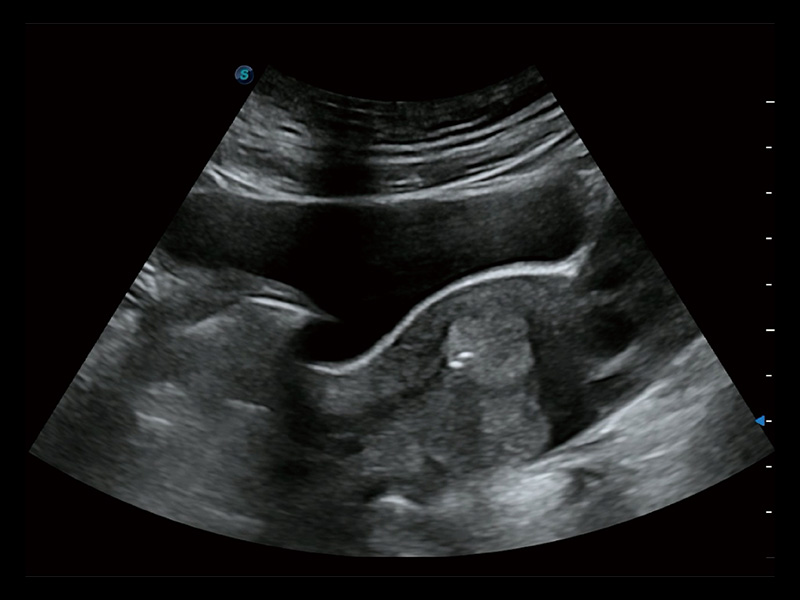

超声引导下双侧卵巢穿刺取卵